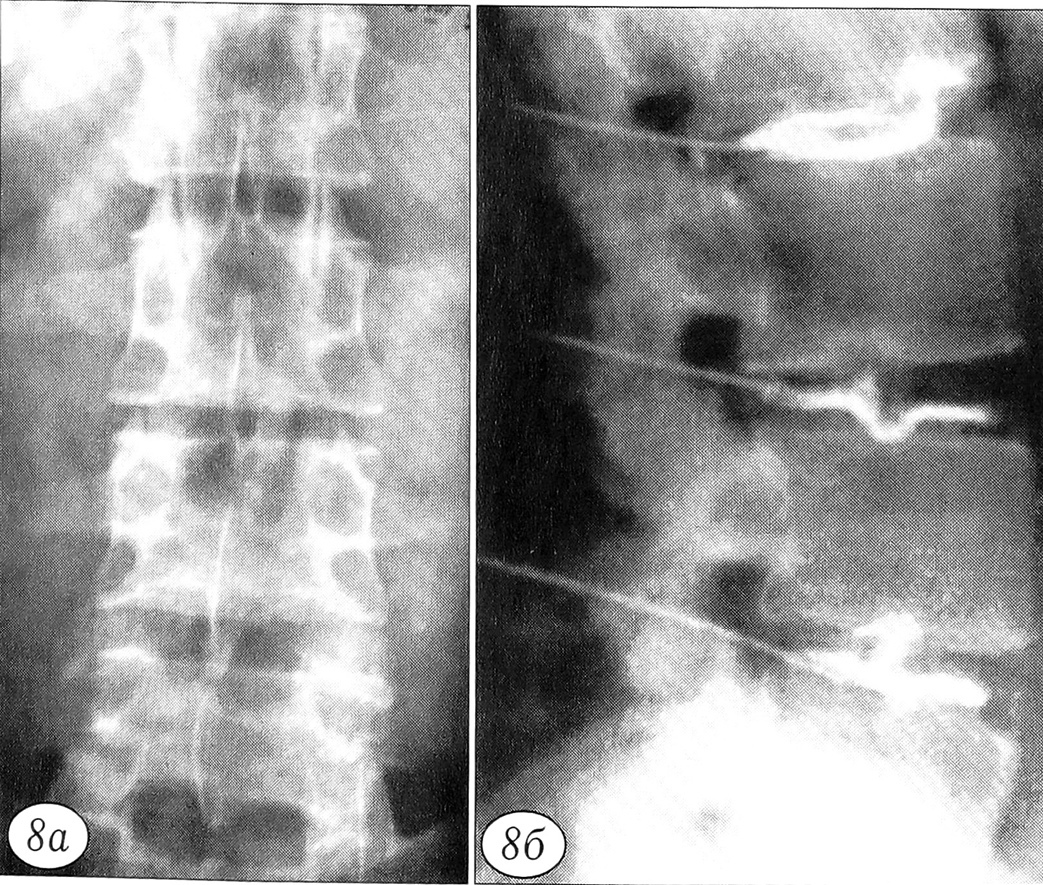

Рис. 6. Эпидурограммы (а — прямая, б — боковая) больного С. 51 года. Исход остеохондропатии позвоночника: фиброз поясничных дисков, диффузный остеопороз, гиперпластический дегенеративный стеноз позвоночного канала — увеличение протяженности контрастированного участка канала при введении стандартного объема контрастного вещества; пятнистость и неровность краев и снижение плотности контрастной тени в центральном отделе позвоночного канала; отсутствие контрастирования латеральных углублений и фораминальных участков; уменьшение заднего эпидурального пространства (за счет гиперплазии дуг и суставных отростков).

Последующие стадии патологического процесса характеризуются соответственно развитием спондилоартроза с гиперпластической деформацией суставных отростков и дуг позвонков (рис. 8) и формированием дегенеративного стеноза позвоночного канала. В дальнейшем, по мере нарастания дистрофических изменений в тканях диска, происходит компенсаторная перестройка губчатой кости тела позвонка: более равномерное восприятие компрессионных нагрузок над всей площадью диска с отсутствием физиологического прогиба замыкательной пластинки сопровождается изменением жесткости трабекулярной кости [18] с появлением участков анизотропии — локального остеопороза и локальной гиперплазии (рис. 9).

Рис. 8. Рентгенограммы (а — прямая, б — боковая) поясничного отдела позвоночника больного О. 28 лет. Диффузная дегенерация поясничных дисков, спондилоартроз.